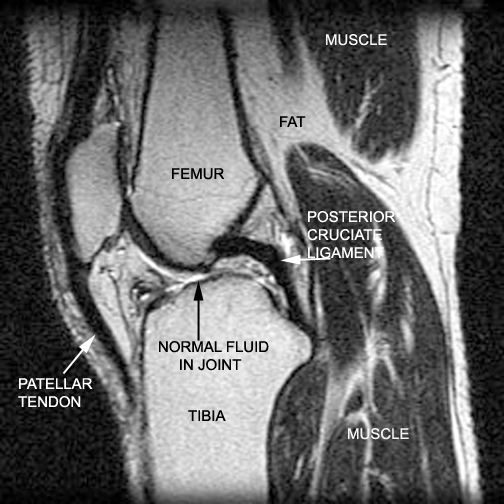

Identify the structures seen. Click the image for labeling.